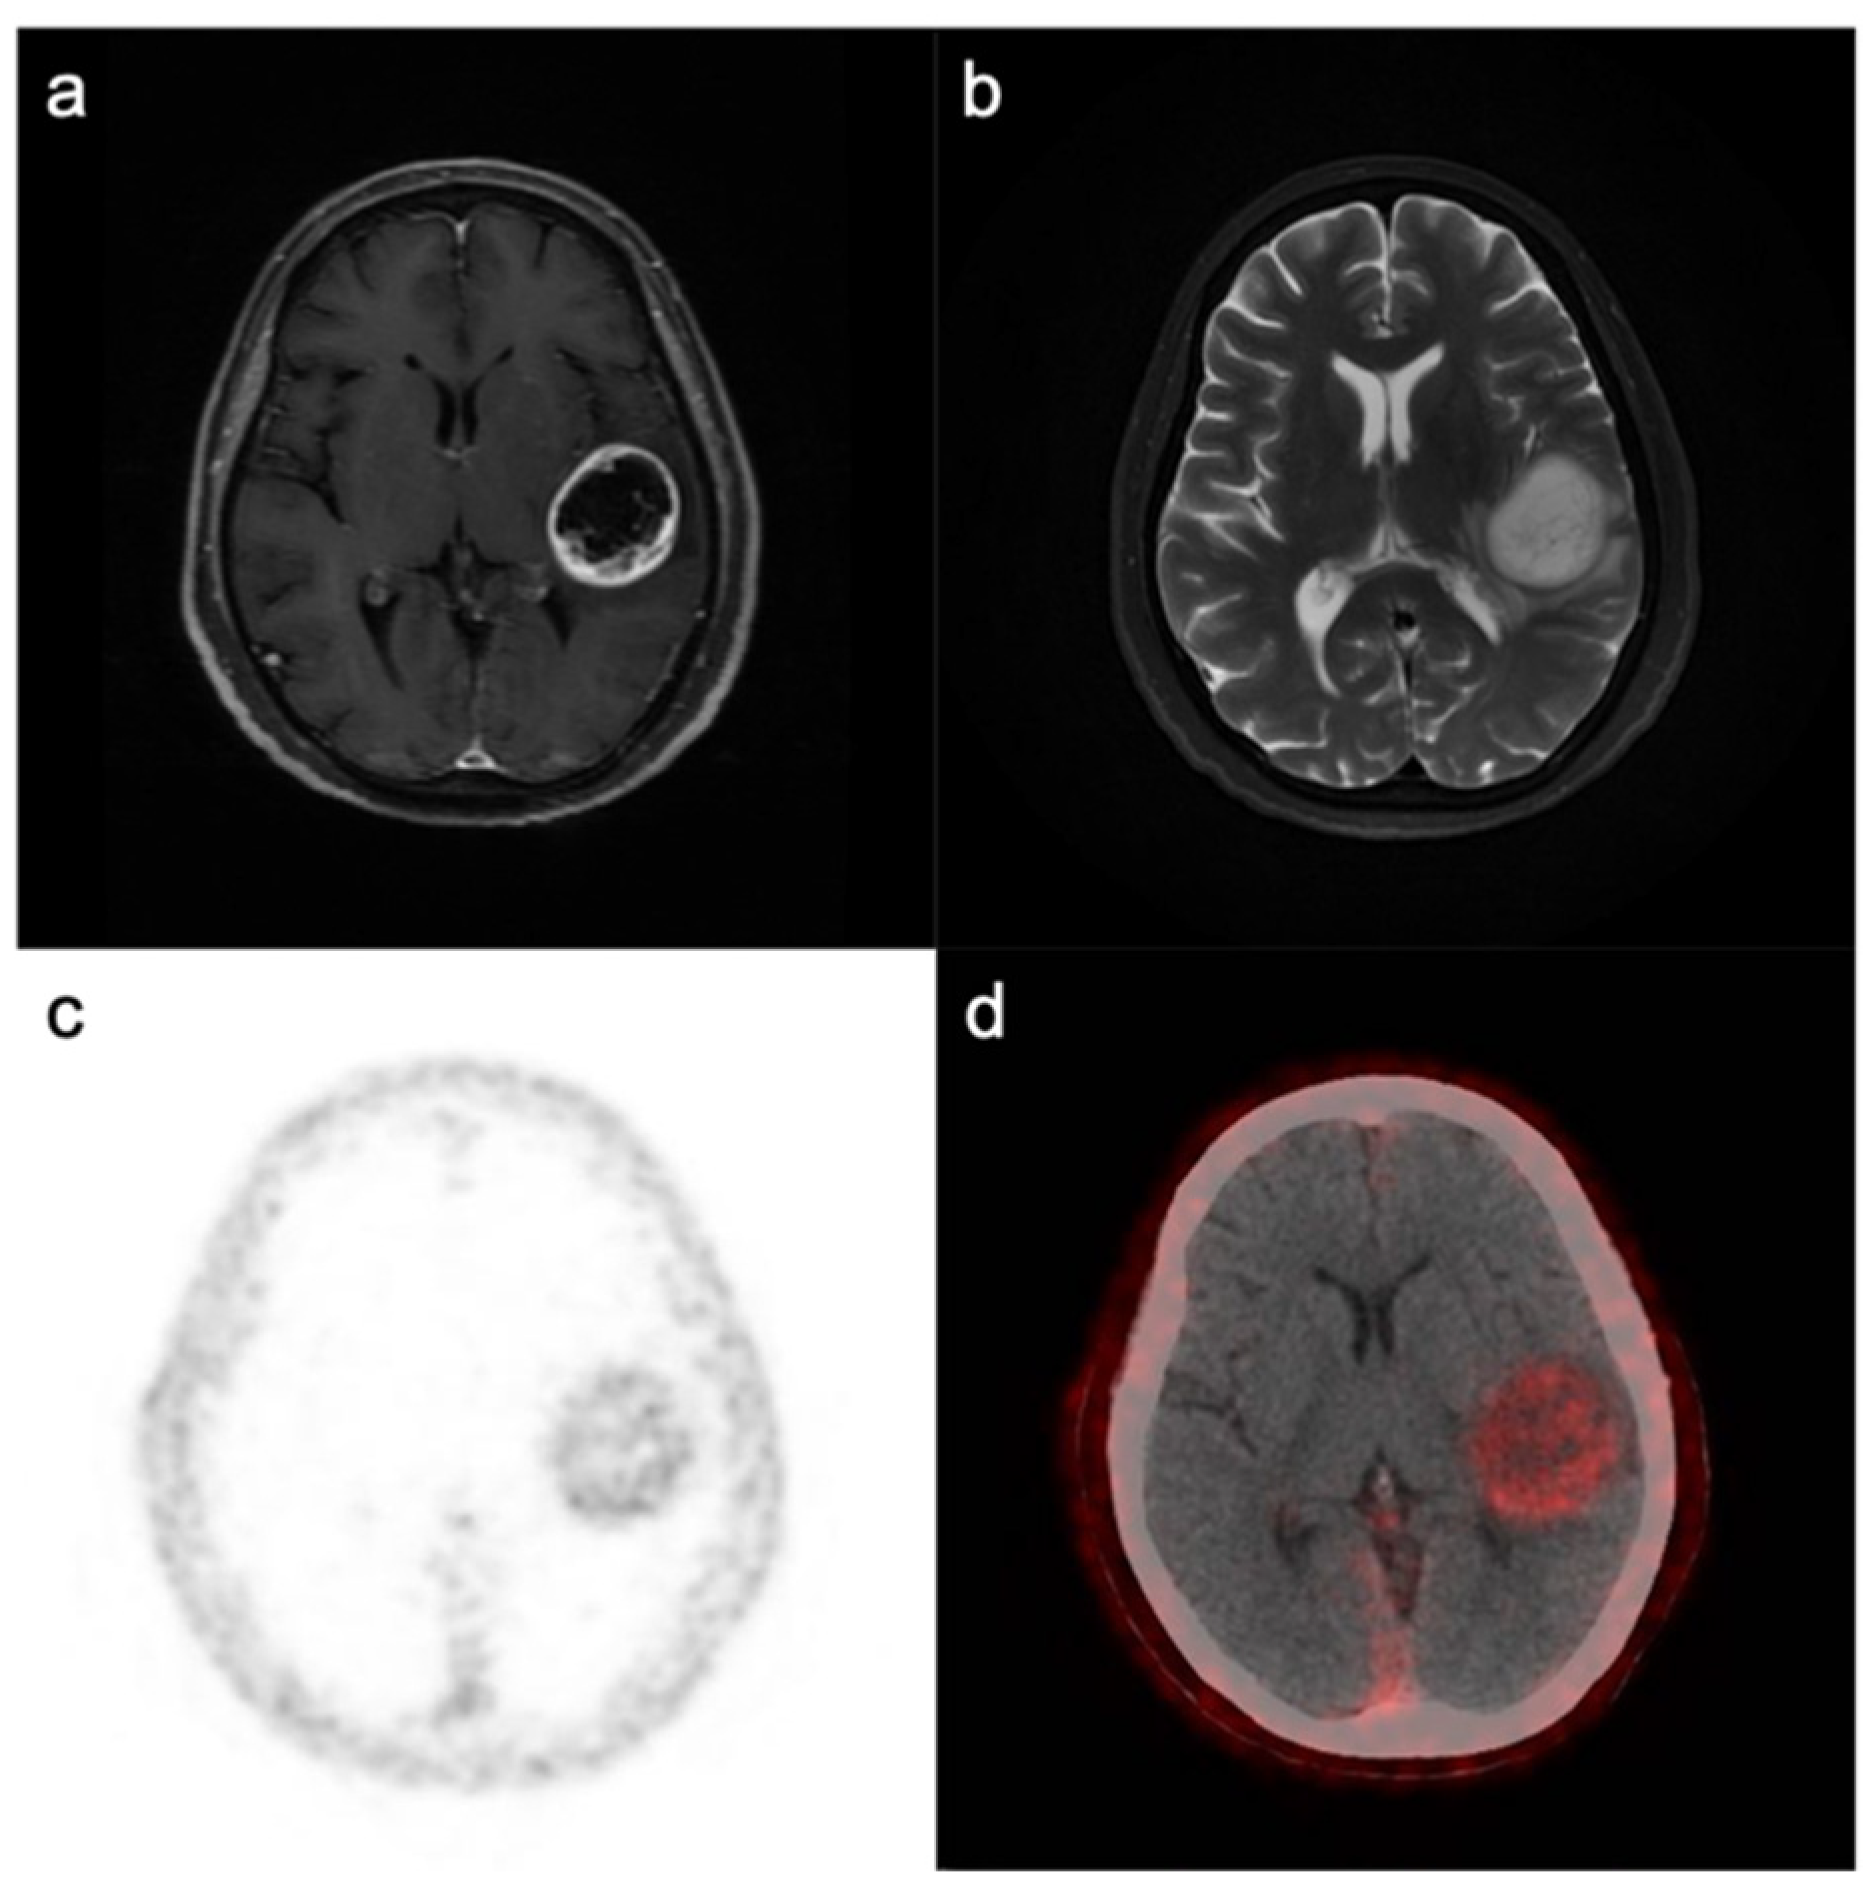

- Rohrich, M.; Loktev, A.; Wefers, A.K.; Altmann, A.; Paech, D.; Adeberg, S.; Windisch, P.; Hielscher, T.; Flechsig, P.; Floca, R.; et al. IDH-wildtype glioblastomas and grade III/IV IDH-mutant gliomas show elevated tracer uptake in fibroblast activation protein-specific PET/CT. Eur. J. Nucl. Med. Mol. Imaging 2019, 46, 2569–2580. [Google Scholar] [CrossRef]

- Rohrich, M.; Floca, R.; Loi, L.; Adeberg, S.; Windisch, P.; Giesel, F.L.; Kratochwil, C.; Flechsig, P.; Rathke, H.; Lindner, T.; et al. FAP-specific PET signaling shows a moderately positive correlation with relative CBV and no correlation with ADC in 13 IDH wildtype glioblastomas. Eur. J. Radiol. 2020, 127. [Google Scholar] [CrossRef] [PubMed]